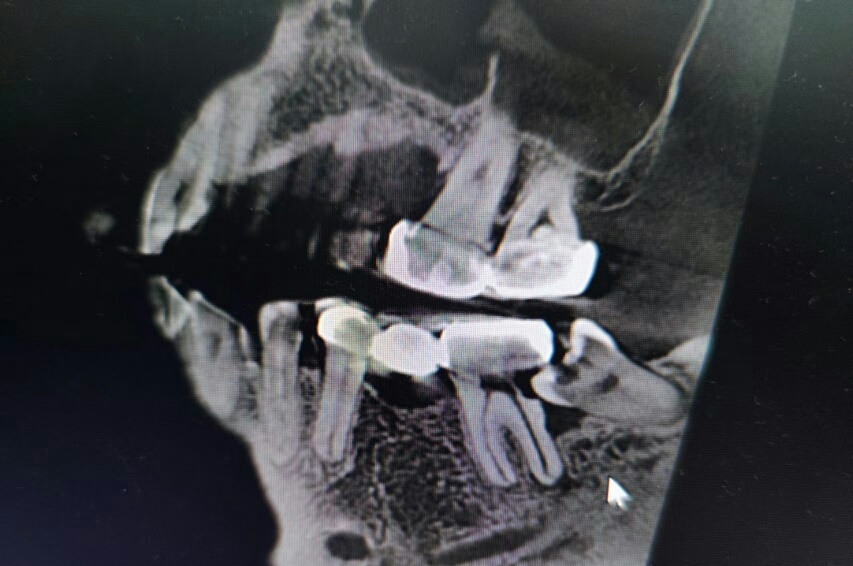

长得太刁钻

这牙齿得去南通某“专业”口腔专科医院治疗。